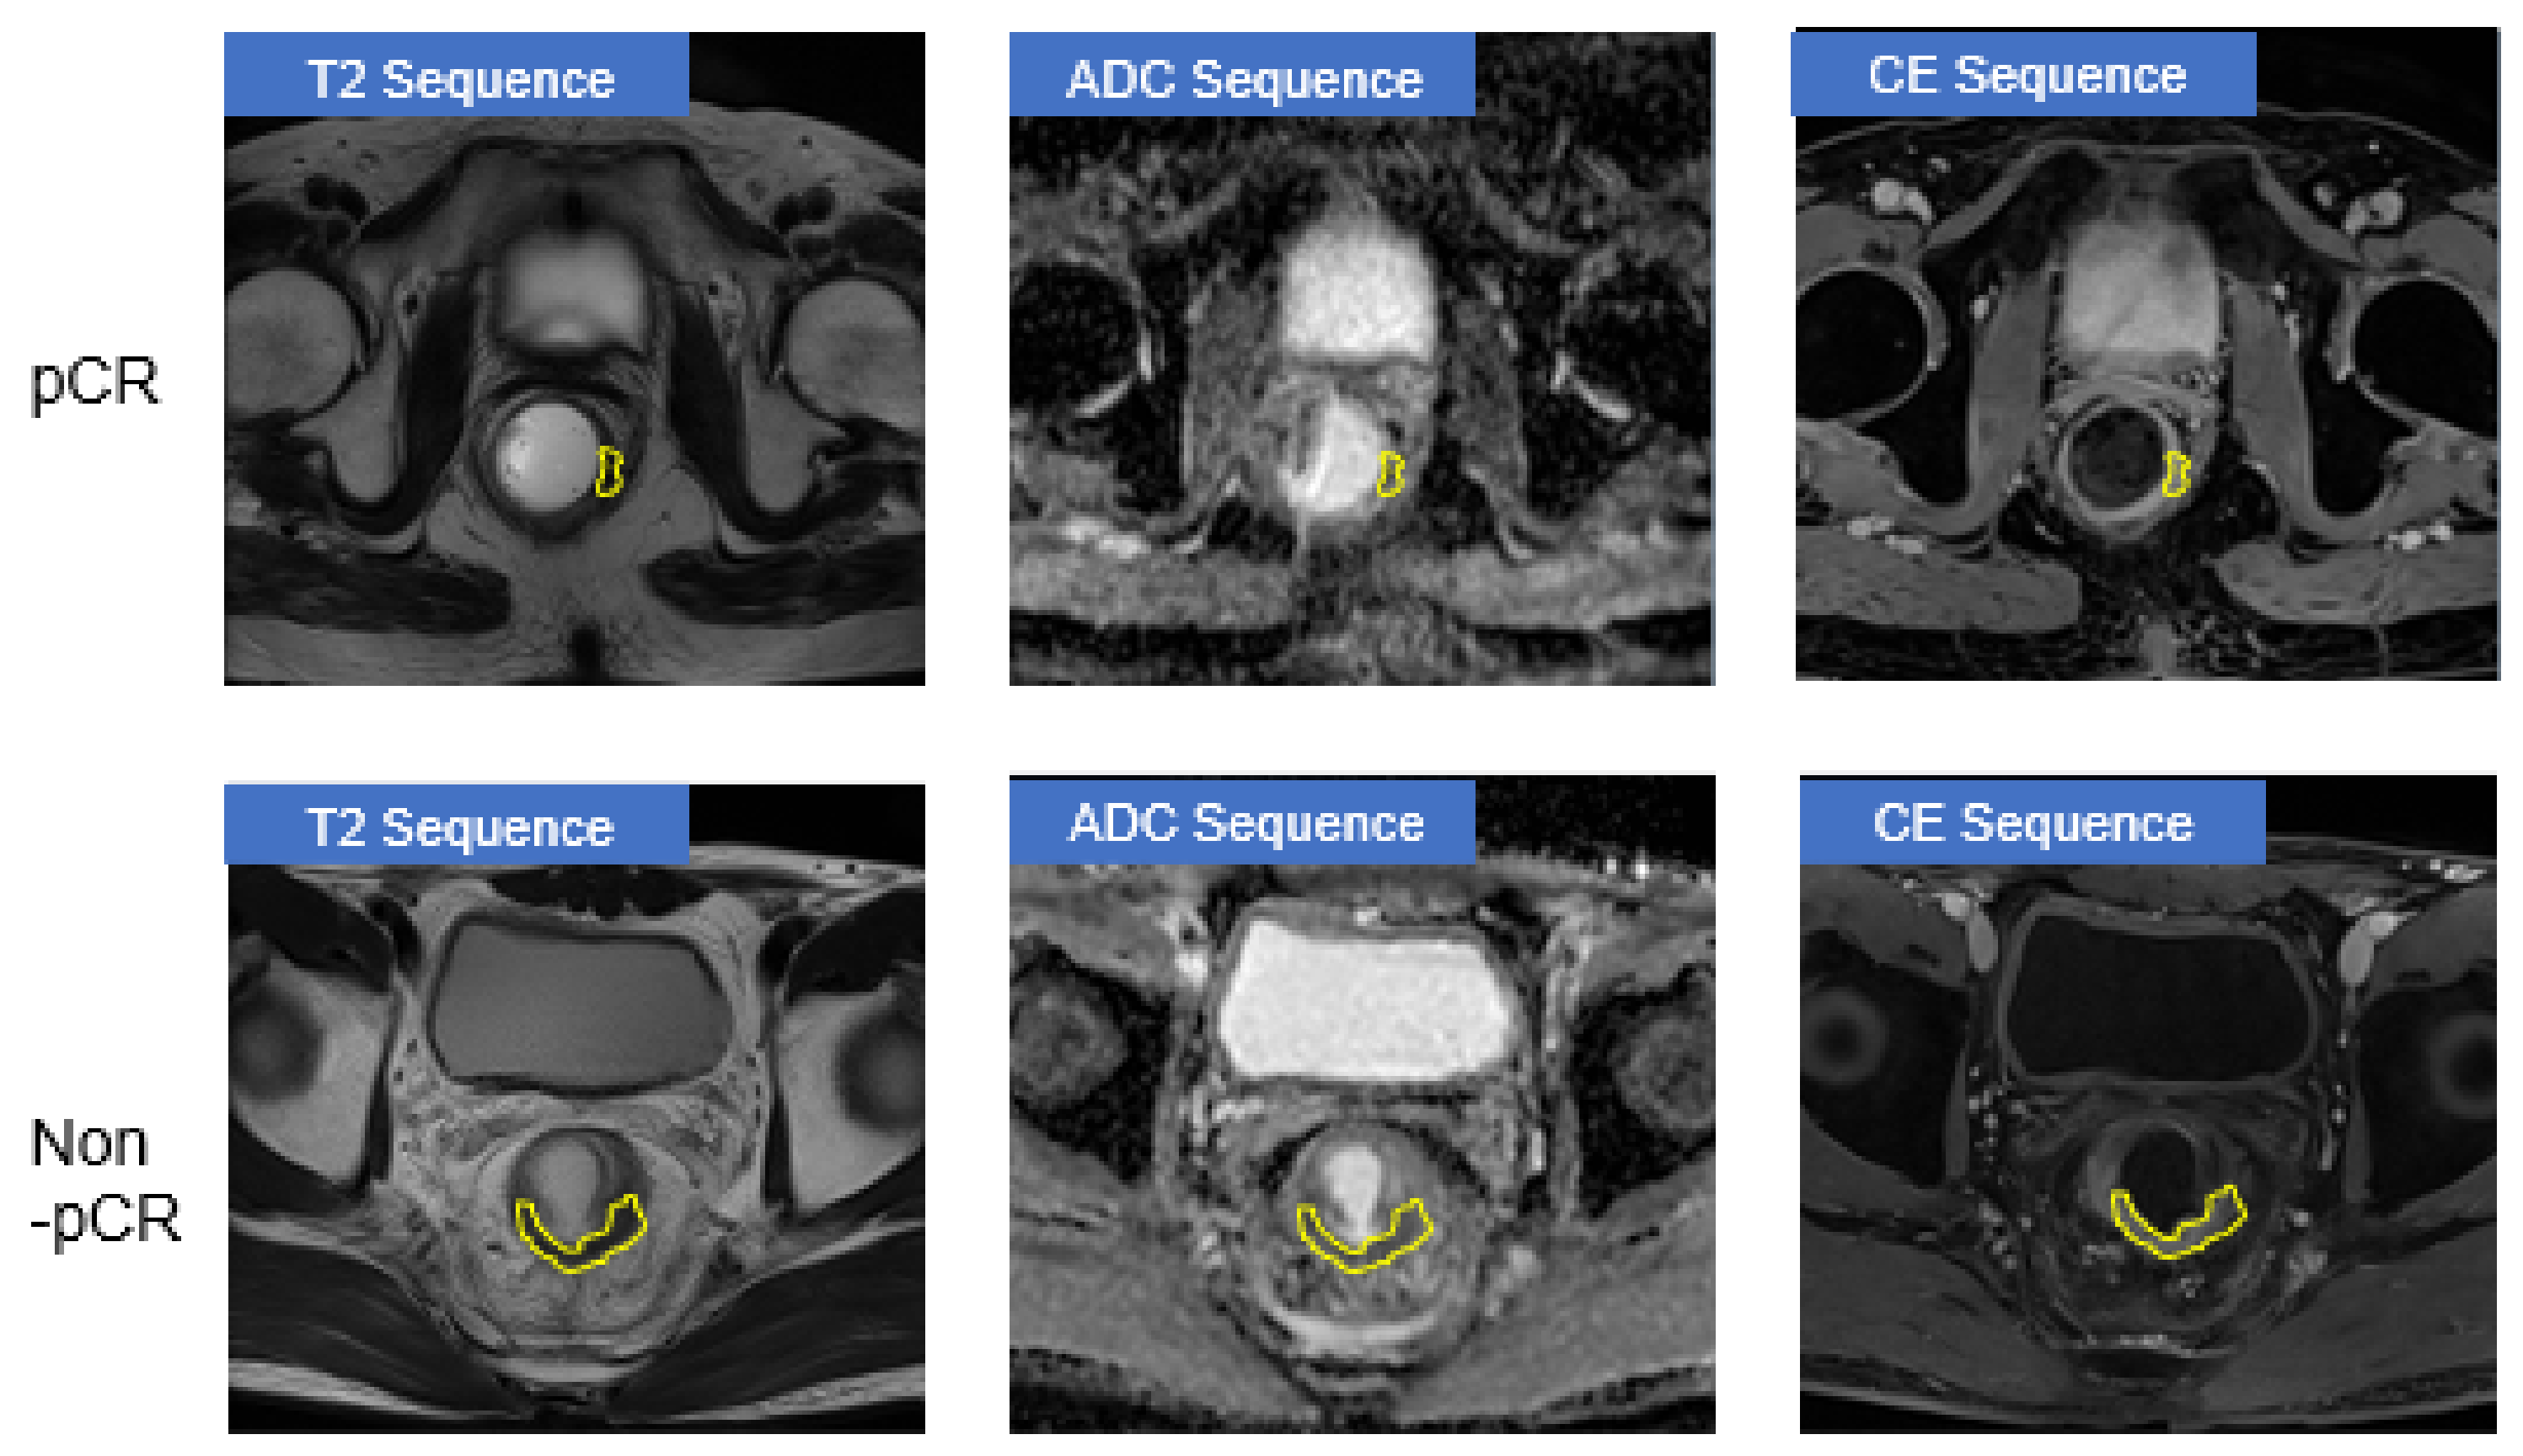

- Comparison of five types of input MRI sequences:

- (a)

- {T2}

- (b)

- {DWI/ADC}

- (c)

- {CE}

- (d)

- {T2, DWI/ADC} and

- (e)

- {T2, DWI/ADC, and CE} (ours).